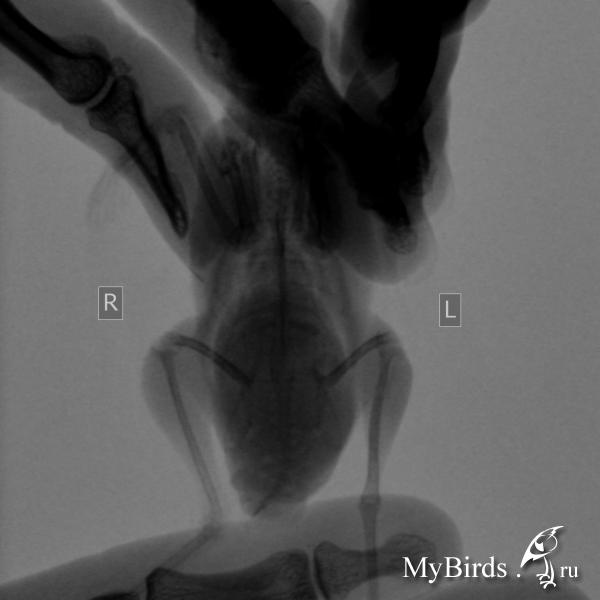

Есть рентген, прилагаю. Очень жду мнения специалиста.

post-42116-1433081614_thumb.jpg

post-42116-1433081628_thumb.jpg

post-42116-1433081652_thumb.jpg

post-42116-1433081673_thumb.jpg

post-42116-1433081688_thumb.jpg

и - срочно - сделать рентген - нужен цифровой, ищите в вет или чел больнице, просите за денги, доза как на хомячка или детскую кисть ребенка, в 2ух проекциях, чтобы разглядеть МЯГКИЕ ткани, снимок выложить на форум- спецы прочтут. (как выложить на форум -см у меня в подписи). Жуть что с животом... ударится не мог? (гематома)

Новообразование вполне может иметь место. тут только пальпация прямая и рентген могут что-то определенное сказать.